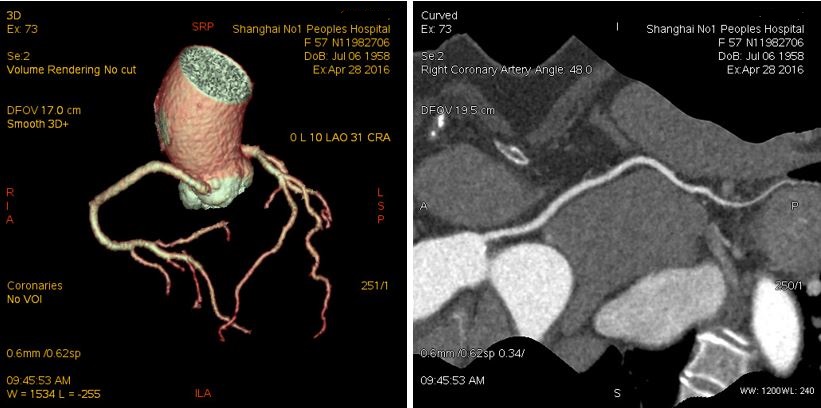

4月28日,冠脉超低剂量扫描,One Beat成像,曝光剂11.96mGry*0.014=0.167mSv!